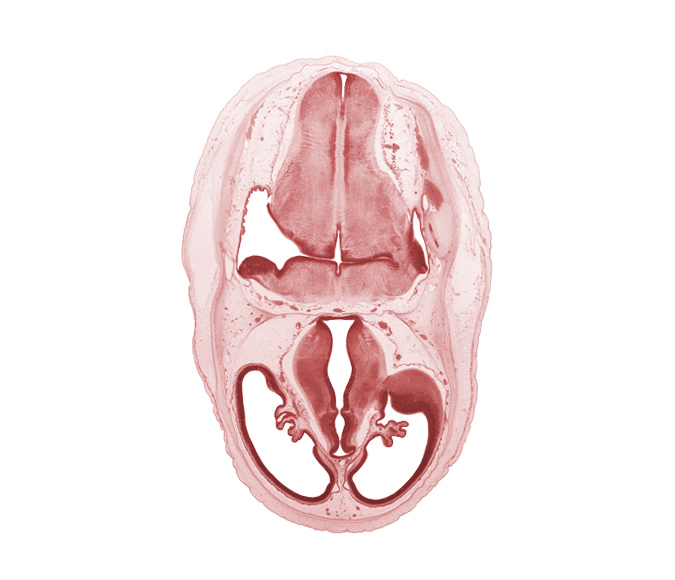

Carnegie Embryo #462 | Location: 4-01-05

Keywords: artifact separation(s), basilar artery, cerebral vesicle (telencephalon), choroid fissure, choroid plexus, dural band for tentorium cerebelli, hypothalamic sulcus, hypothalamus, lateral ventricle, marginal ridge, obex, oculomotor nerve (CN III), osteogenic layer, pons region (metencephalon), posterior dural venous plexus, primordial sigmoid sinus, venous plexus(es), ventral thalamus

Source: The Virtual Human Embryo.